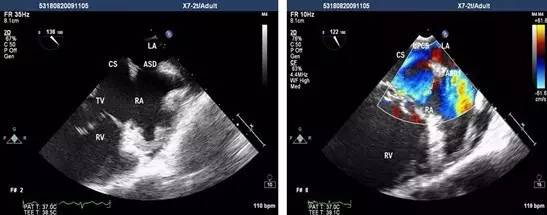

经食管超声心动图是将超声探头置入食管内,从心脏的后方向前近距离探查其深部结构,避免了胸壁、肺气等因素的干扰,故可显示出清晰的图像,提高对血汗管疾病诊断的敏感性和可靠性。

为什么经食道超声心动图就能发现心房血栓呢?因为食管位于左心房后面,绝大部分人食管与左房后壁都有接触。

通过食管置入超声探头,就能很直观的从左心房后面看到心房里面的结构,能够看清心房、心耳内有无血栓。

而如果使用普通经胸的心脏彩超看心房,超声波需要穿过皮肤、肌肉、骨骼、肺等组织,就很难分辨清楚心房内有无血栓。